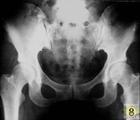

褐黄病性关节炎是一种少见的氨基酸代谢障碍的遗传性疾病。病人肝脏中缺乏黑尿酸氧化酶,导致大量未经氧化分解的黑尿酸由尿中排出和沉积于人体各种组织和器官里。如黑尿酸沉积在关节结构组织中,则引起褐黄病性关节炎。